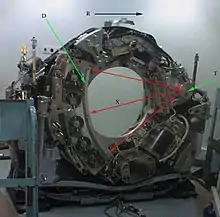

C-Arm CT

- C-arms fluoroscopy systems can implement back-projection using images acquired at different angles around the patient[32]. The X- ray beam is collimated to a large cone with an XRT and image receptor rotated as one to acquire projections from a large number of slices simultaneously. An approximate back projection reconstruction technique known as the Feldkamp algorithm is generally applied. The result is a full 3D image acquisition in a single rotation about the patient. Multi-Detector CT (MDCT) scanners use this approach with an array of detectors (e.g. 64 rows and 800 columns) - and are sometimes referred to as Multi-Detector Row scanners. C-arm fluoroscopy systems also use a broad-area image receptor but of much larger size, e.g. 1,920 dels in 2,480 columns.

- C-arm systems can therefore acquire data simultaneously for a much larger number of projections. A disadvantage, however, is that imaging with broad-area exposures generates a substantial amount of scattered radiation[33] so that tomographic images do not have the resolving capacity for low subject contrasts that is achievable with MDCT. Computerised scatter corrections are therefore applied to address the issue. Another disadvantage is that the Feldkamp algorithm only performs well for small fields of view, e.g. the head and neck. Its application to larger body areas involves handling truncated projections, which can be addressed using more sophisticated computational methods[34].

- Similar designs have also found application in dental radiography[35].

- The imaging geometry for C-Arm CT is illustrated in Figure 7.15. The XRT and image receptor take images from different angles around the patient at a magnification of ~1.5. Partial rotations of 150-200o have been found to be adequate - not the full 360o as in helical CT. In addition, rotations can be in orbital as well as oblique planes. Rotation speeds of 30o per second and imaging frame rates of 7.5-10 frames per second are typically used to acquire 50 or more 2D projections.